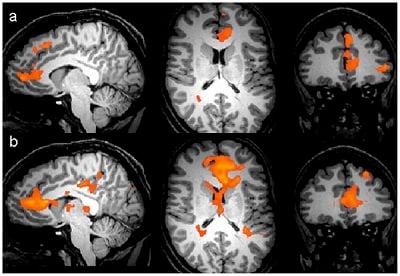

Sagittal, axial and coronal views of areas of statistically significant BOLD activation (p = 0.005 uncorrected, cluster threshold 8 voxels) for the condition ‘self – queen’ in (a) the depressed group (n = 13) and (b) the control group (n = 14). Areas in red represent regions of increased BOLD activity in the ‘self’ as opposed to ‘queen’ condition. Credit May Sarsam, Laura M. Parkes, Neil Roberts, Graeme S. Reid, and Peter Kinderman/PLOS ONE.

“That’s not too surprising, but the brain scans also revealed significantly greater blood oxygen levels in the medial superior frontal cortex – the area associated with processing self-related information – when the depressed participants were making judgments about themselves.

Dr May Sarsam, from the Mersey Care NHS Trust, said: “This study explored the difference in medical and psychological theories of depression. It showed that brain activity only differed when depressed people thought about themselves, not when they thought about the Queen or when they made other types of judgements, which fits very well with the current psychological theory.